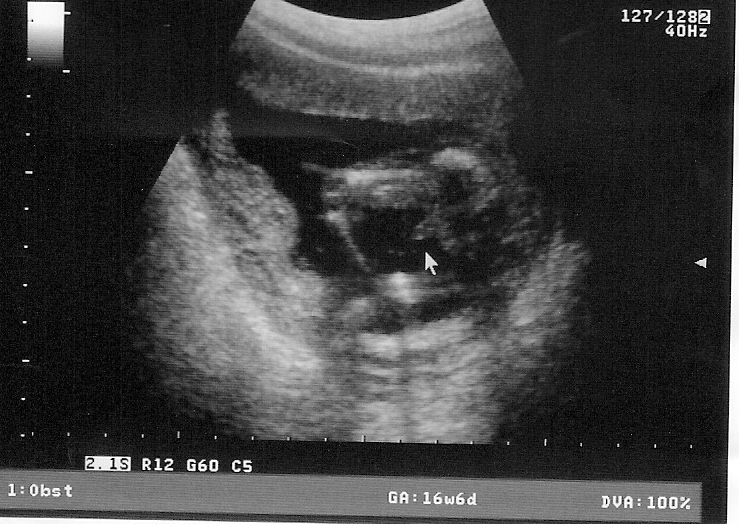

Confirmed this morning, by ultrasound. It’s a boy. Which means, because the wife just has to have a little girl, who according to her will have “big boobs and long hair and be absolutely gorgeous”, a cute little creature that she can spend hours and hours and hours dressing and playing with, an addition that I would have to build a new closet for, I have to go through this damn pregnancy shit yet again. More early morning nausea. The totally irrational mood changes. The “oh, you carry this because I’m pregnant” shit. The even worse “Oh you change his diaper because I’m pregnant” shit. And, the unintended weight gain, not her, but me. God knows I have to eat out of sympathy when she gorges. Which is almost on an hourly basis. But, there are advantages to having another little guy in the family; more to play Left 4 Dead with on the computers, and, savings of unknown amounts of hundreds of dollars when the wife can’t buy baby Louis Vuitton purses. Yes, they make those for little girls….

Little guy, code named “Boris 2”, is due May 10, or somewhere thereabouts. Not sure what to name him, but, oh, we’re thinking about, um, “Richard”. Easy to remember, just like the other little guy, and yes, me. By the time I’m done, I’m going to put George Foreman to shame...